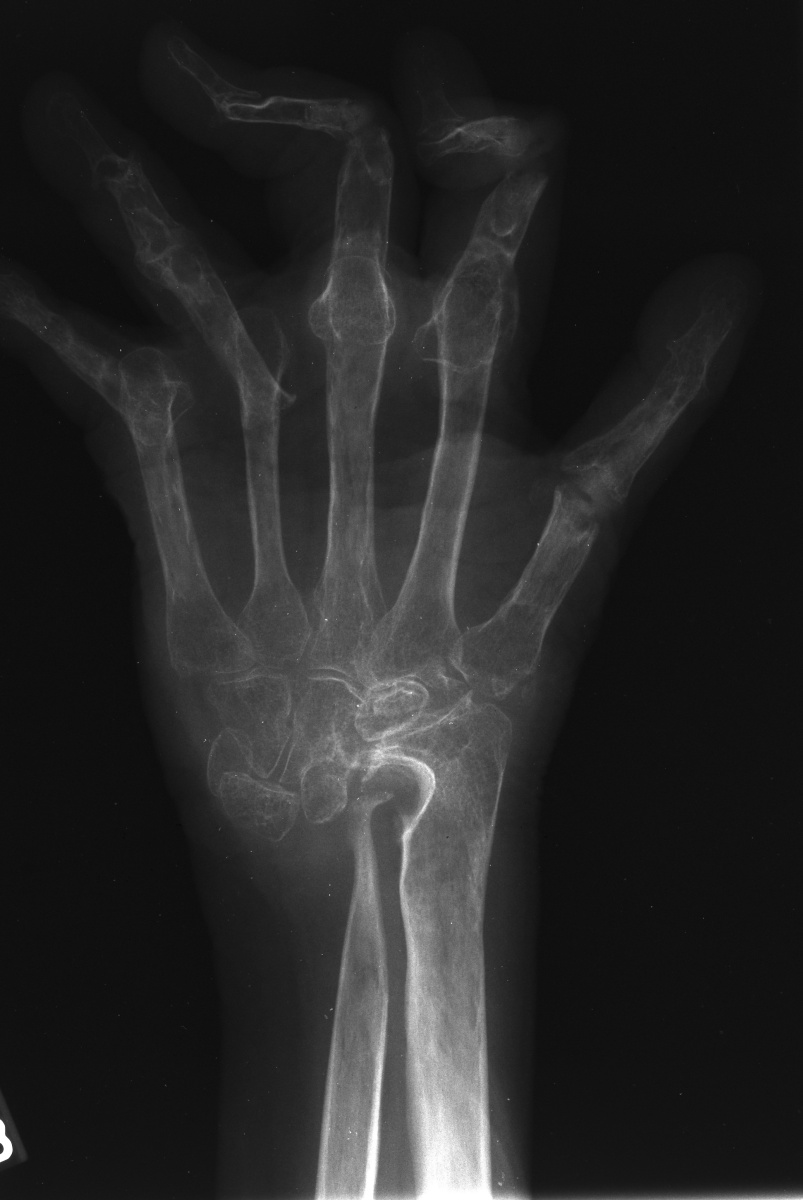

Xrays show radiocarpal collapse, proximal migration of the proximal phalanges, flail PIP joints and loss of the proximal half of the dorsal cortex of the proximal phalanges.

Her greatest desire was pinch reconstruction. This was approached in two stages: wrist fusion, implant removal and fusion of the index and middle PIP joints, followed by index and middle MCP arthroplasties. There are several alternative approaches, including index MCP fusion and revision PIP arthroplasties.

Below are xrays after the first set of reconstructions.

For the second stage of her reconstruction, the index proximal phalanx did not have adequate dorsal cortex to support an implant arthroplasty, and bone graft from the metacarpal head was used to reconstruct this.

Final radiographs, three months postoperative.